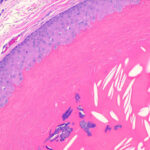

The epithelial cells close to the cystic cavity appear swollen and are filled with pale cytoplasm . These swollen cells do not produce a granular layer but generally undergo abrupt keratinization, although nuclear remnants are occasionally retained in a few cells. The content of the cysts consists of homogeneous eosinophilic material . |

Whereas focal calcification of the cyst content does not occur in epidermal cysts, foci of calcification are seen in approximately one fourth of trichilemmal cysts . A considerable foreign-body reaction results when the wall of a trichilemmal cyst ruptures, and the cyst may then undergo partial or complete disintegration. |

Trichilemmal cysts frequently disclose small, acanthotic foci in their walls that are indistinguishable from solid areas, as seen in a proliferating trichilemmal cyst . The association of a trichilemmal cyst with tumor lobules of a proliferating trichilemmal cyst is also seen occasionally . |